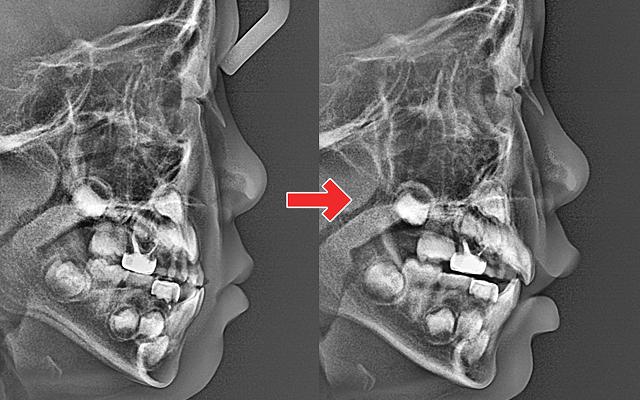

성장기에는 교정 시기

치료의 절반입니다.

턱 성장 방향과 교합을 조기에 바로잡아

평생 바른 치열과 얼굴 균형을 만듭니다.